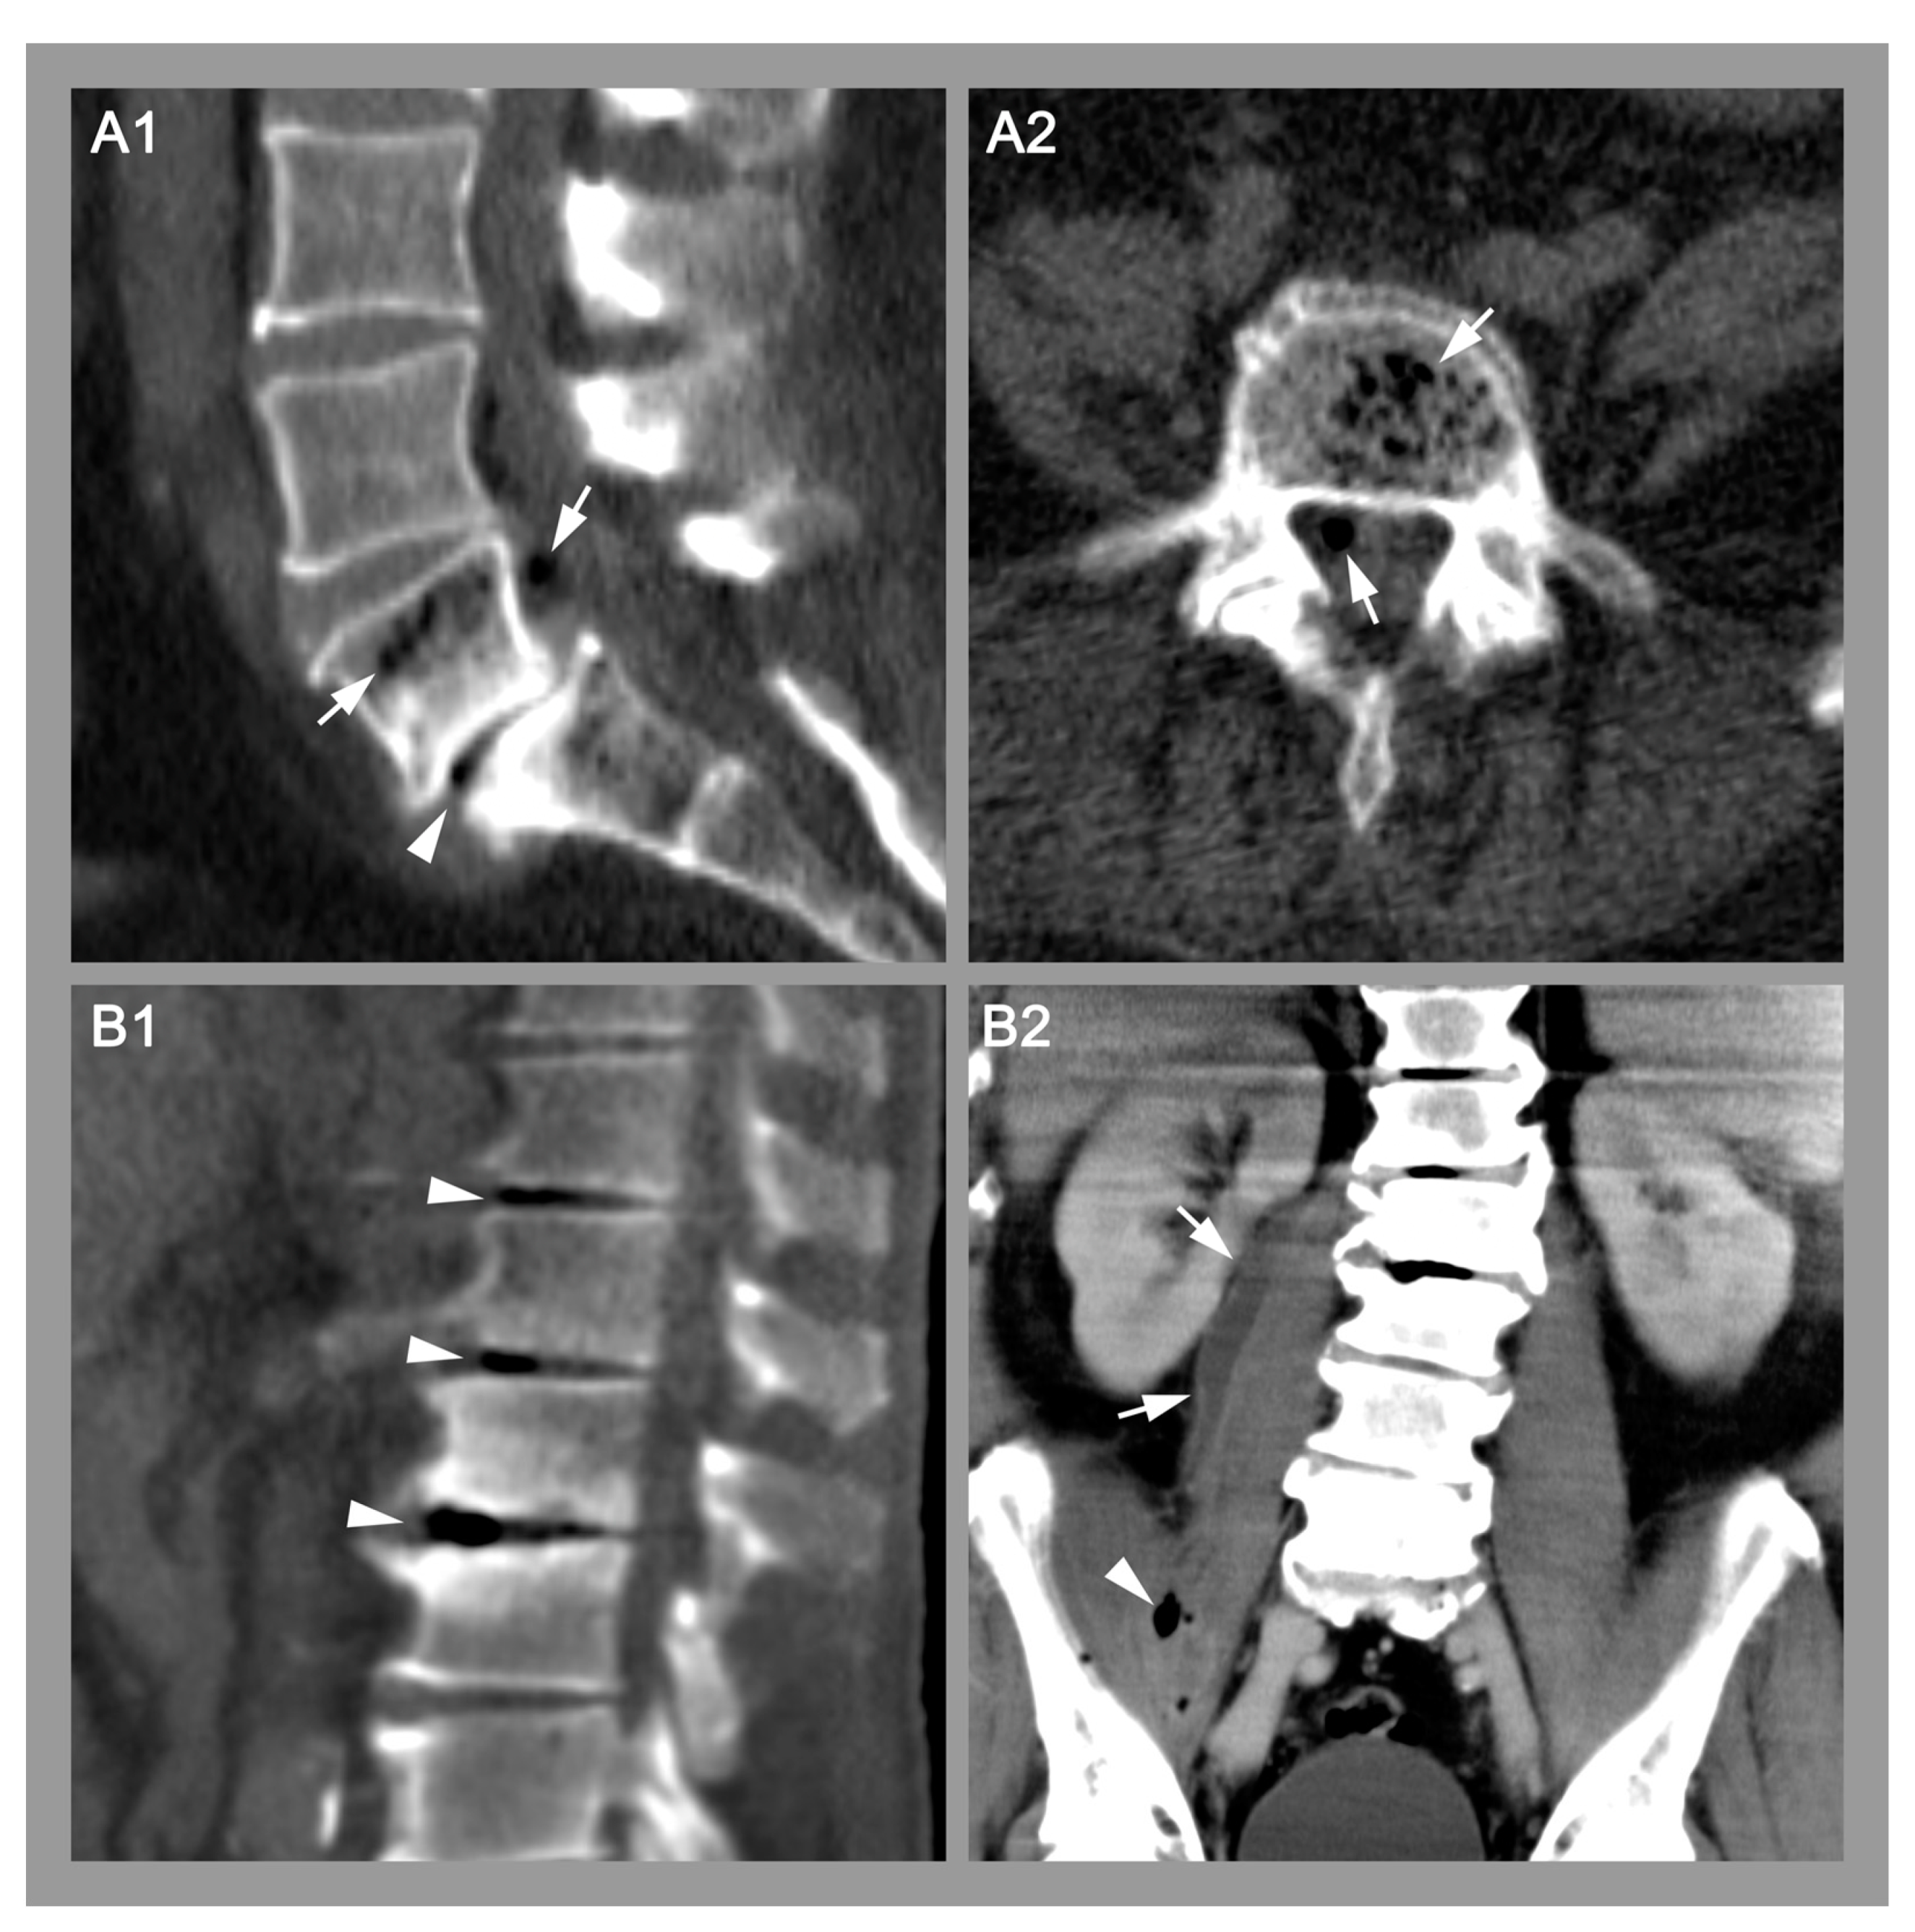

Gas within the Intervertebral Disc Does Not Rule Out Spinal Infection—A Case Series of 135 Patients with Spontaneous Spondylodiscitis